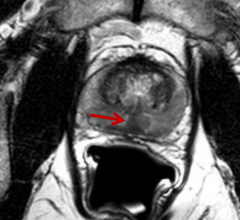

News and new technology innovations concerning how imaging technology can help diagnose and treat prostate cancer can be found on this channel.